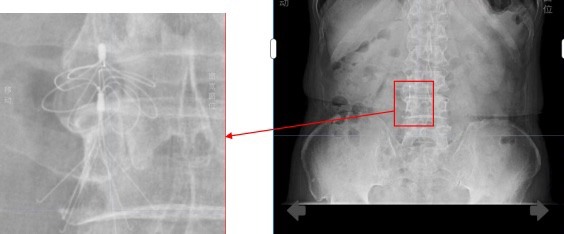

当时,因严重下肢静脉血栓,王大爷接受了下腔静脉滤器植入术,这枚金属滤器如同一张“血管防护网”,曾有效拦截血栓,守护了他的生命。可如今,它却成了房颤导管消融手术的“拦路虎”——该手术常规路径需经大腿股静脉,通过下腔静脉进入心脏,但滤器恰恰堵住了这条必经之路。若强行通过可能导致滤器移位、血管破裂或血栓脱落,风险极高。加上滤器植入时间过长,取出滤器的风险同样不亚于手术本身。

经过对影像资料反复推演,团队终于为王大爷量身定制了创新方案:经右侧颈内静脉入路,在三维超声引导下实施零射线房颤射频消融术。

手术当天,在轻柔音乐的舒缓下,陈雄彪团队开始了这场精细操作。首先,他在王大爷右侧颈部完成毫米级精准穿刺,将导管经上腔静脉送入右心房。

随后,手术最关键的一步——房间隔穿刺开始了,他在无X线透视的情况下,仅凭三维超声影像,将导管安全穿过心房之间的墙壁,进入左心房,每一步都需极度谨慎,“就像在黑暗中仅凭手感与地图穿越迷宫。”陈雄彪说。

历经约4小时,三维系统显示:两侧肺静脉电位完全消失,异常电传导被彻底阻断——这意味着房颤的“根源”已被成功隔离,手术成功了。